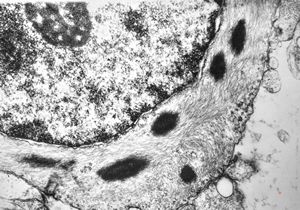

rabbit spinal cord trauma

rabbit spinal cord trauma